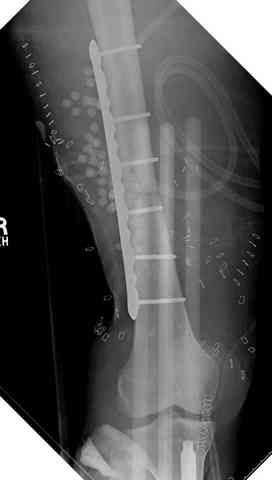

После пары Irrigation& Debridment с вакуумом можно провести окончательную фиксацию интрамедуллярным методом. Чем быстрее, тем лучше, потому что сроки нахождения наружных фиксаторов на конечности тоже имеют значение, риск осложнения увеличивается после длительного пребывания наружного фиксатора.

Открытые переломы, если имеется хороший доступ из раны можно сопоставить и зафиксировать первично пластиной, потому что несопоставленные переломы намного труднее репонируется в поздние сроки. Активизация больного за счет стабилизации кости благоприятно влияет на сращение, а также облегчается манипуляция по закрытию дефекта.

Необходимо доказать проникновение инфекции в кость, иначе агрессивные сегментарные остеотомии кости удлиняет процесс восстановления.

Показания к применению мышечно-ротационной пластики на голени являются обнаженный фрагмент кости, мышца, прикрывая кость восстанавливает питание, а снаружи мышца служит ложем для кожной пластики.

здесь случай с политравмой, перелом зафиксирован наружным фиксатором, после третьей irrigation&debridment фиксация бедра пластиной с последующей кожной пластикой.

Djoldas Kuldjanov, MD